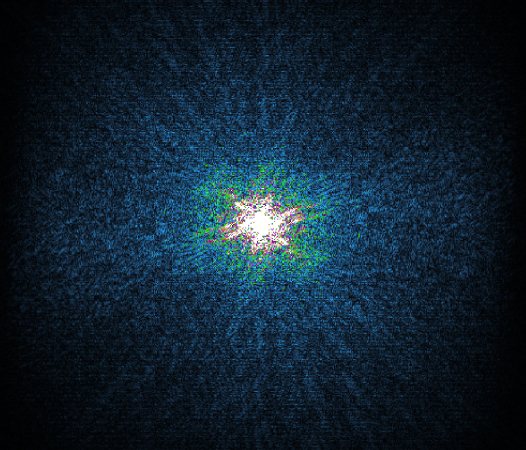

In the example below, only one fifth of the required MR radiofrequency signals is recorded. This results in a five times faster acquisition, with a subsampled k-space (top left) and inherent image artifacts after standard reconstruction (top right).

K-space

K-space compressed sense

The Compressed SENSE reconstruction then uses iterative, knowledge-based algorithms to fill in the empty lines in k-space (bottom left). This removes the artifacts while keeping the final image fully consistent with the acquired data (bottom right).